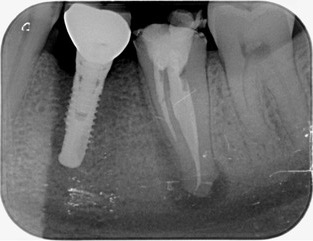

Cas clinique n°1 - Avant / Après